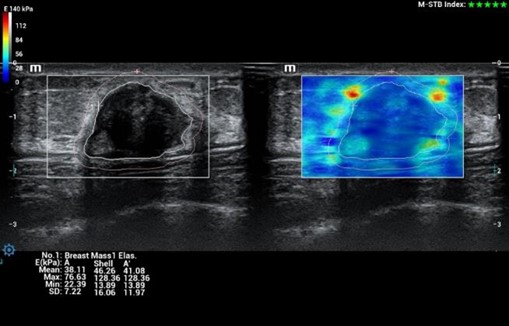

STE - Sound Touch Elastografia, 2D shear wave elastografia v reálnom čase

HiFR STE (Shear wave elastografia🙂 ZST+ UZV platforma umožňuje 10 krát rýchlejší STE frame rate ako u štandardných UZV prístrojov pri zachovaní hladkosti a konzistentnosti obrazu. Senzitívnejšia detekcia pohybu, lepšia stabilita vyššia presnosť. Unikátny M-STB index indikujúci pohybovú stabilitu obrazu. Presná kvantifikácia tuhosti pečene pomáhajúca pri gradingu a prognóze fibrózy a cirhózy pečene

HiFR STE Elastography: Kompletná a výkonná elastografia. Shear Wave Elastografia (HiFR STE, STQ). Strain - Natural Touch Elastografia (NTE). Vysoká citlivosť, penetrácia a presnosť. Unikátna “shell” analýza hodnotiaca infiltráciu tumoru do okolia. Automatické ohraničenie ložiska a shear wave kvantifikácia tuhosti tkaniva. Presné posúdenie tuhosti tkaniva pomôže v diagnostickom odlíšení malígneho a benígneho nálezu.

HiFR STE Elastography: Kompletná a výkonná elastografia. Shear Wave Elastografia (HiFR STE, STQ). Strain - Natural Touch Elastografia (NTE). Vysoká citlivosť, penetrácia a presnosť. Unikátna “shell” analýza hodnotiaca infiltráciu tumoru do okolia. Automatické ohraničenie ložiska a shear wave kvantifikácia tuhosti tkaniva. Presné posúdenie tuhosti tkaniva pomôže v diagnostickom odlíšení malígneho a benígneho nálezu.

STE - Sound Touch Elastografia, 2D shear wave elastografia v reálnom čase